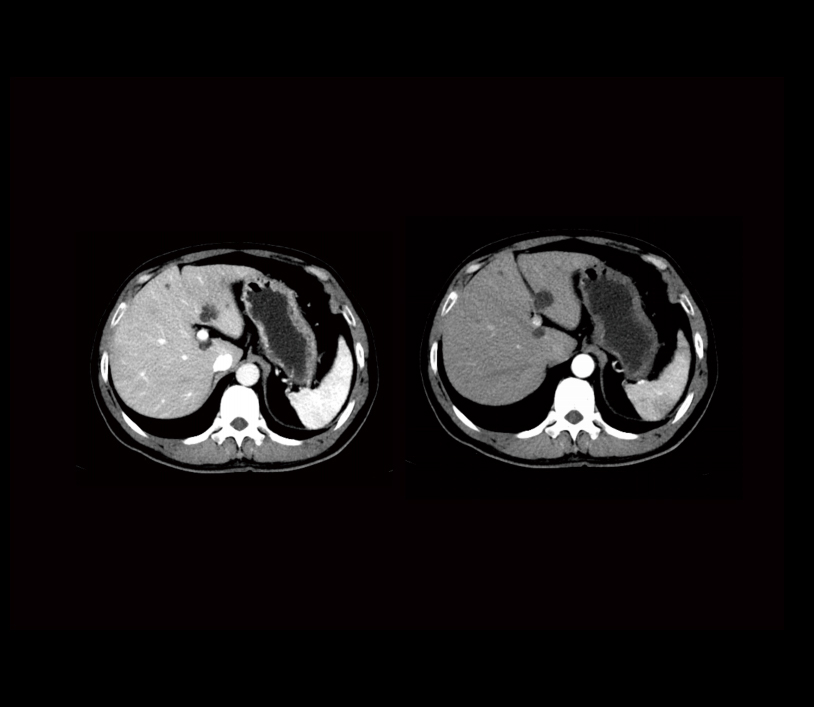

配套光子算法集 - 精准诊断配套光子算法集,高清真实的还原人体组织精细结构;图灵Z-IMAGE后处理平台满足医生对图像进行后处理的需求,轻松应对3D立体成像。 | ![]() |